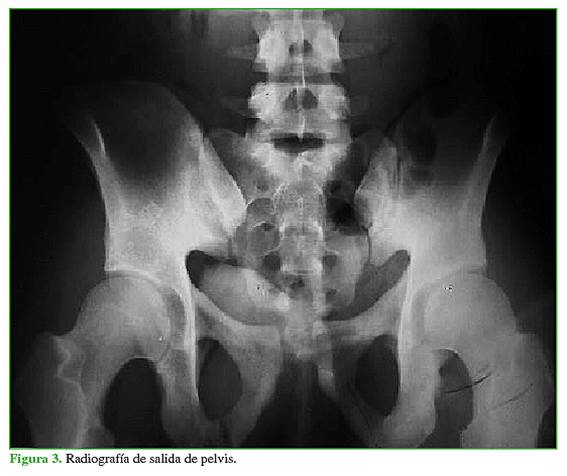

Las fracturas se clasificaron, según la clasificación de Young y Burgess, en las radiografías panorámica (Figura 1), de entrada (Figura 2) y de salida de pelvis (Figura 3), y tomografía computadorizada.